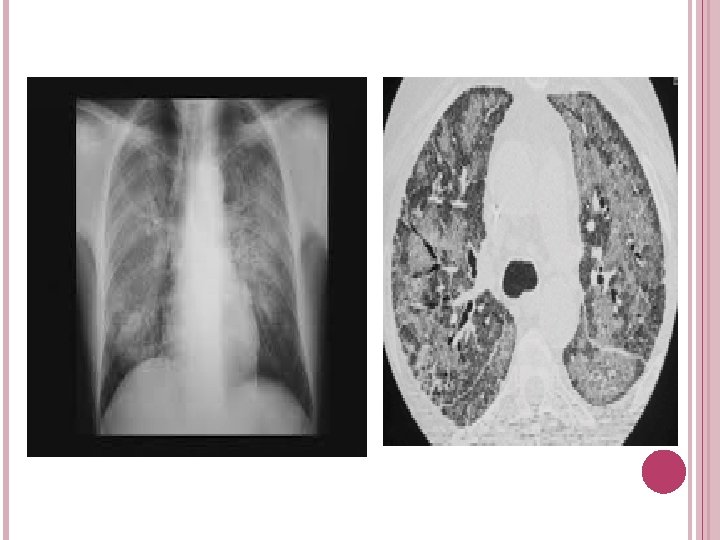

MANIFESTATIONS RESPIRATOIRES AU COURS DE L'INFECTION PAR LE VIRUS DE L'IMMUNODÉFICIENCE HUMAINE Pneumocystose Pneumocystis jiroveci *La symptomatologie initiale est discrète toux sèche et d'un décalage thermique *À un stade plus évolué, des râles crépitants des opacités avant tout interstitielles, mais aussi alvéolaires, bilatérales, . *Au stade ultime d'insuffisance respiratoire aiguë, un aspect de « poumons blancs »